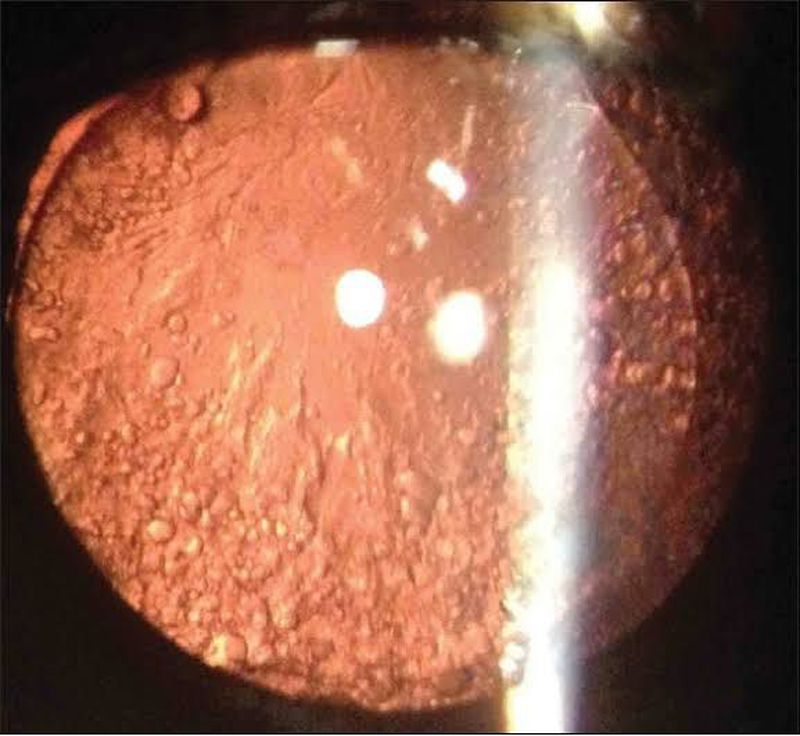

This variety of aftercataract occurs typically in eyes with very little or no postoperative inflammation. It is due to random proliferation of the cells which produce lens fibres, along the posterior capsule.These aborted lens fibres glisten like precious stones in retroillumination